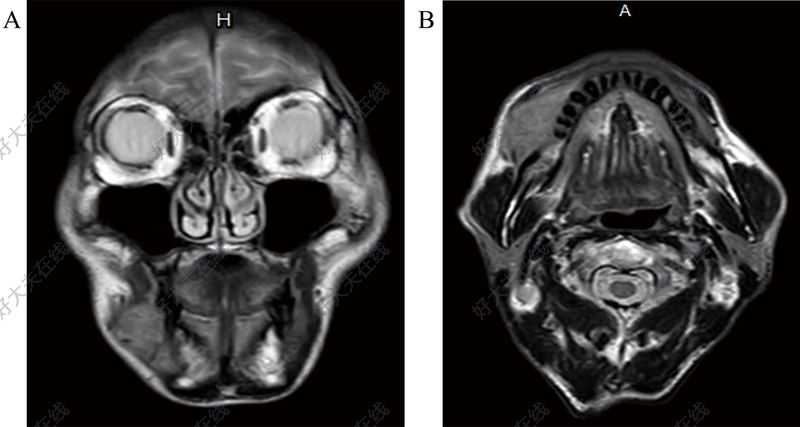

治療前 中年患者,50歲,牙齦癌侵犯下頜骨。術(shù)前評(píng)估,需行下頜骨體部截?cái)嘈郧谐?,同時(shí)伴有口內(nèi)軟組織缺損。 治療中 使用髂骨肌皮瓣,一蒂雙島,修復(fù)復(fù)雜缺損,重建下頜骨建立,同時(shí)修復(fù)口內(nèi)缺損。 治療后 治療后365天 術(shù)后一年+復(fù)查,下頜骨重建良好,高度可,咬合關(guān)系良好,張口度可,生活基本正常。